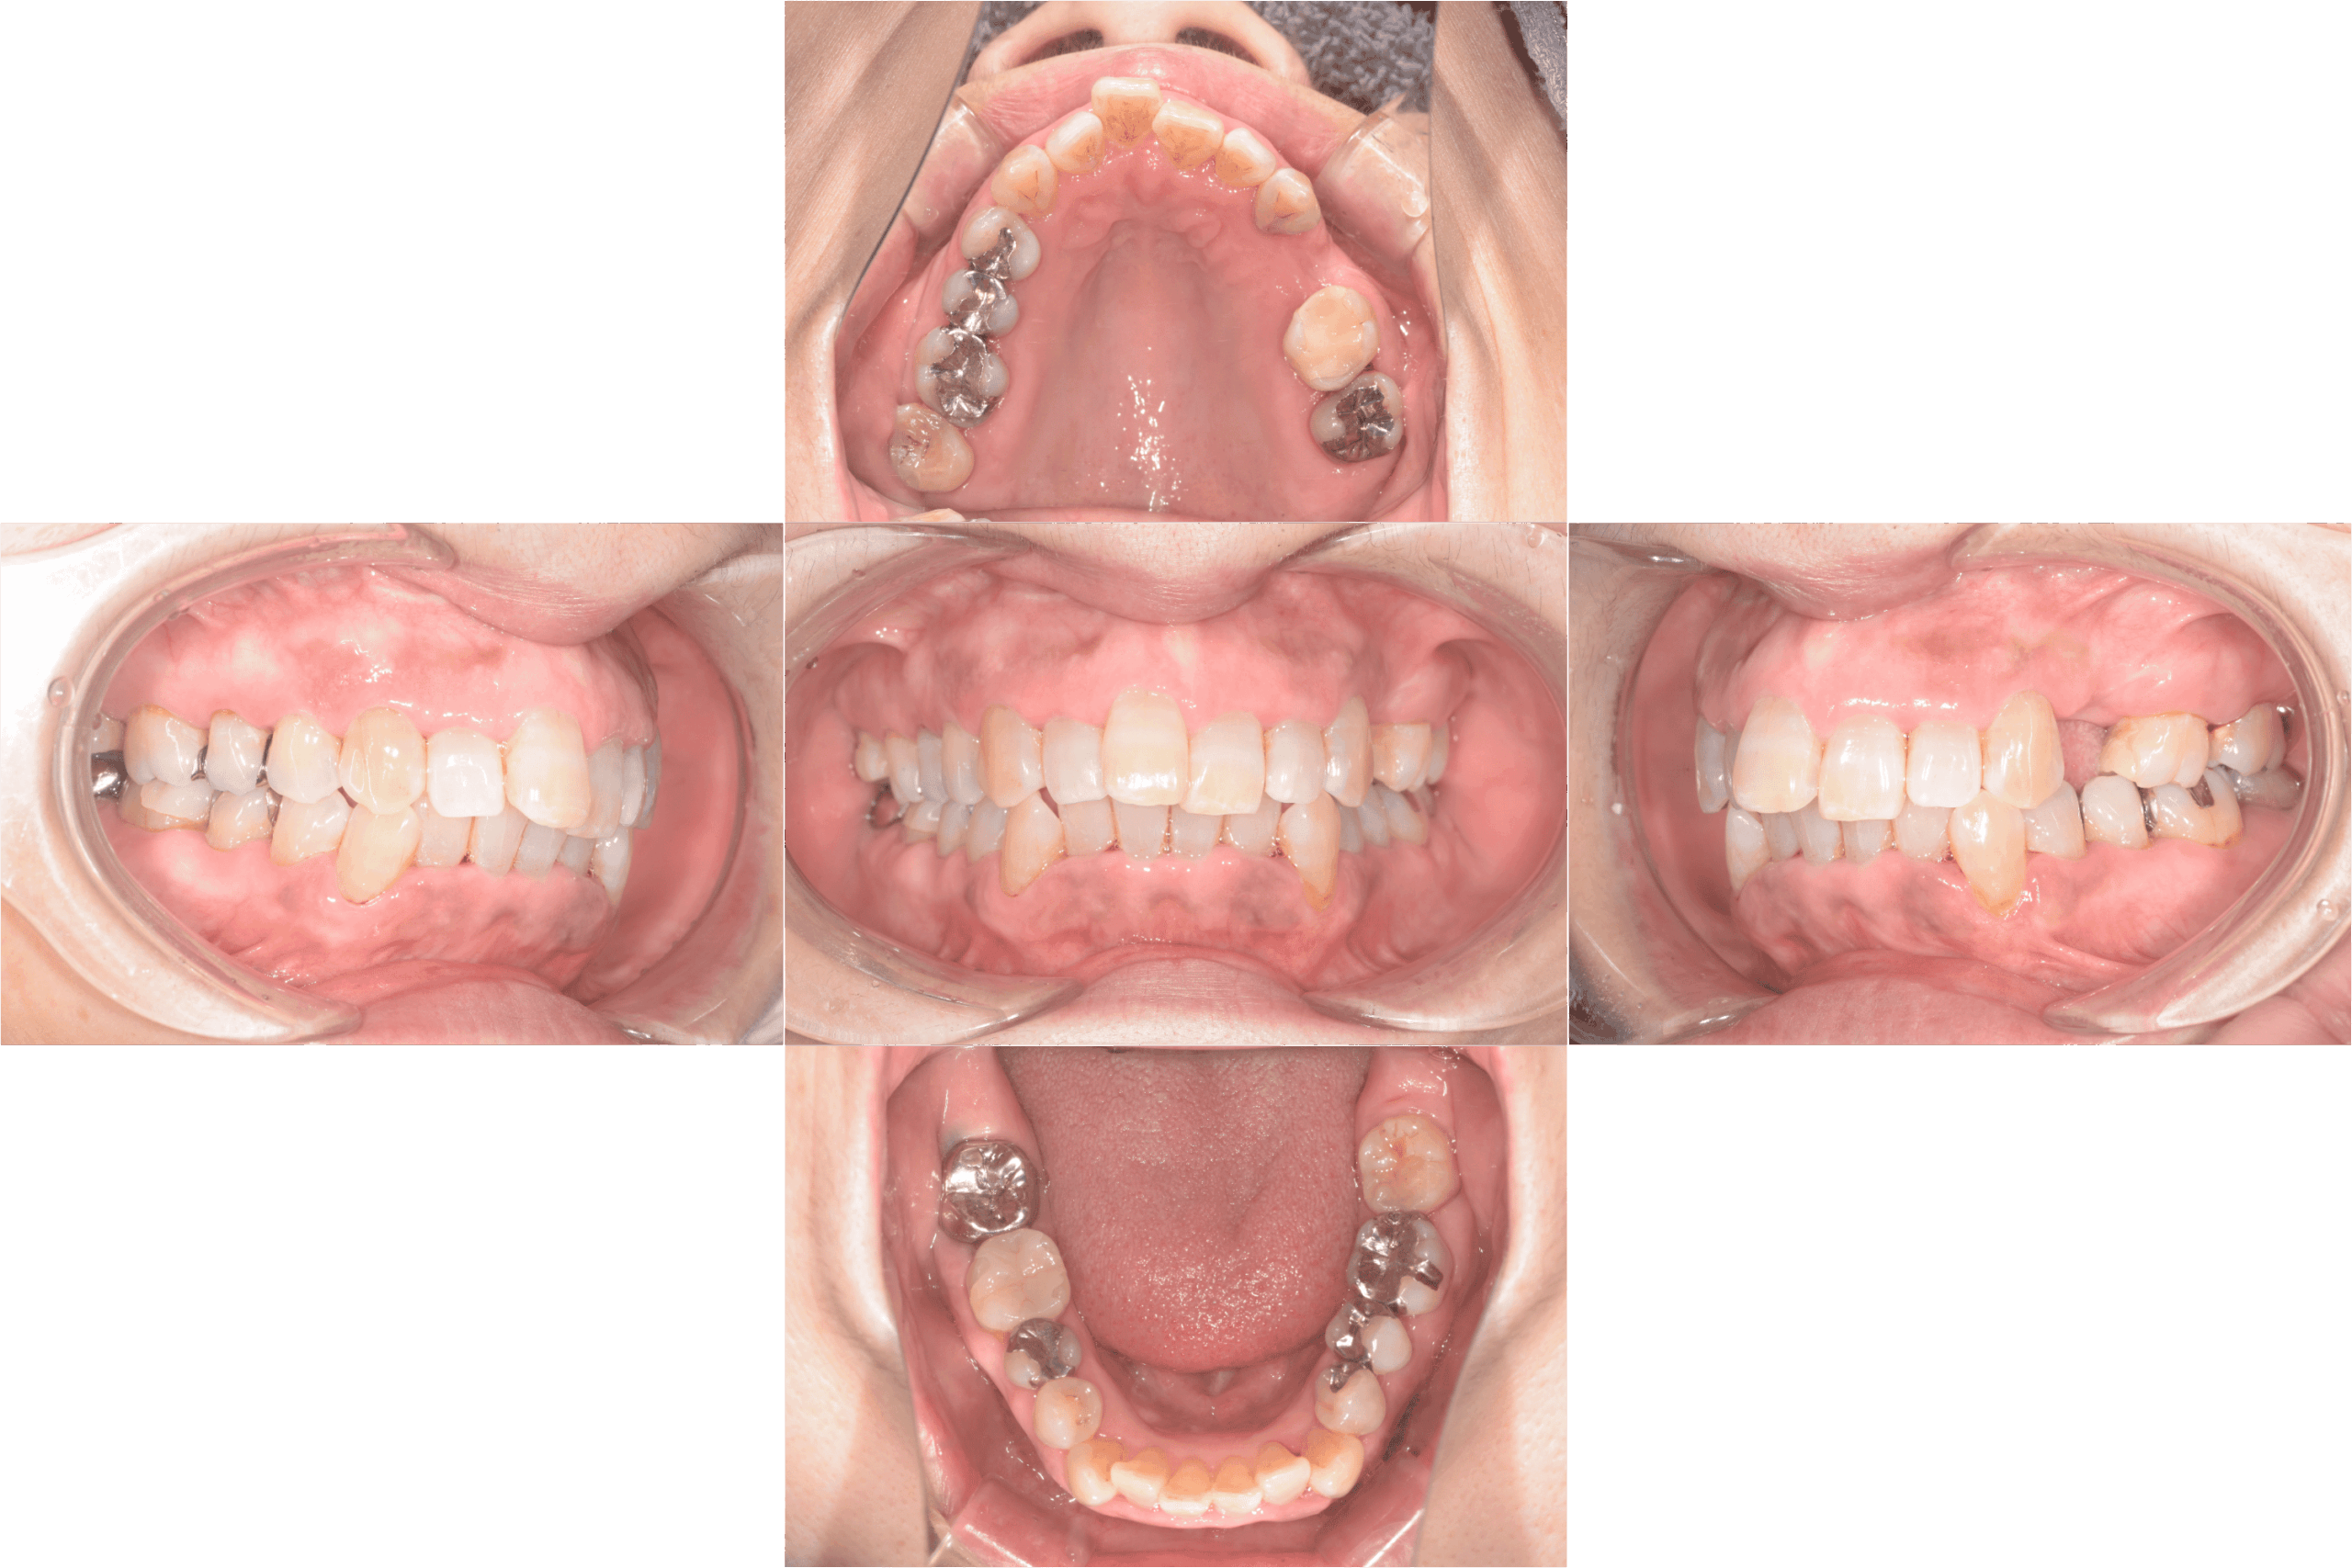

治療前口腔内写真

治療後口腔内写真